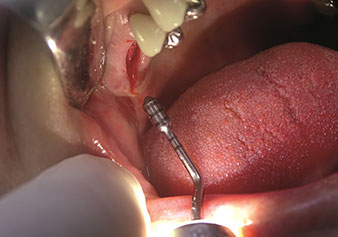

Sıklıkla hafife alınan uygulamalardan biri, alveolar yönetimin bir parçası olarak diş köklerinin veya kök parçalarının nazikçe çıkarılmasıdır. Şu anda iki modeli (W&H'ten EX1 ve EX2) mevcut olan hassas periotomlarla, özel olarak endodontik ön işleme tabi tutulmuş dişler veya ankilozik kökler de kolayca çıkarılabilir. Sonuç, sert ve yumuşak dokuları tamamen sağlam olan ekstraksiyon alveolleridir, çünkü genellikle onları açmak gerekli değildir.

Bu, daha sonra veya hemen implant bakımı için optimum bir temel oluşturur [şekil 1 ve 2, Dr. Torsten Conrad’ın (Bingen a. Rhein) onayı ile kullanılmıştır].

Fotoğraf: © Dr Torsten Conrad (Bingen a. Rhein)